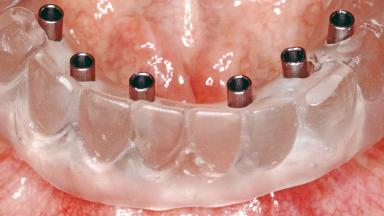

Conventional Loading of Six Implants in the Mandible and Final Restoration with a Full-Arch Metal-Ceramic FDP

SAC Level Complex

Defining Characteristics Fully edentulous lower jaw to be rehabilitated with an implant-borne fixed dental prosthesis

Loading Protocol Conventional/early

Retention Screw-retained, with 4 or more splinted implants Screw-retained, with 4 or more splinted implants

Inter-Arch Distance Adequate